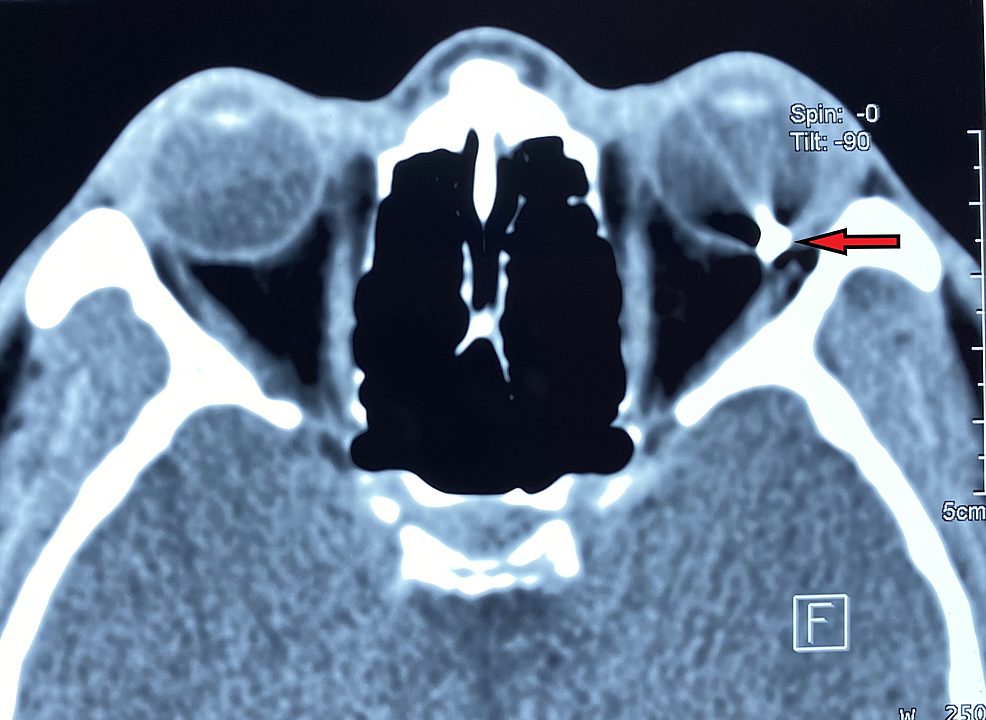

图表 5 眼眶 CT 显示眼内异物,呈现金属伪影。(图源:参考文献 7)